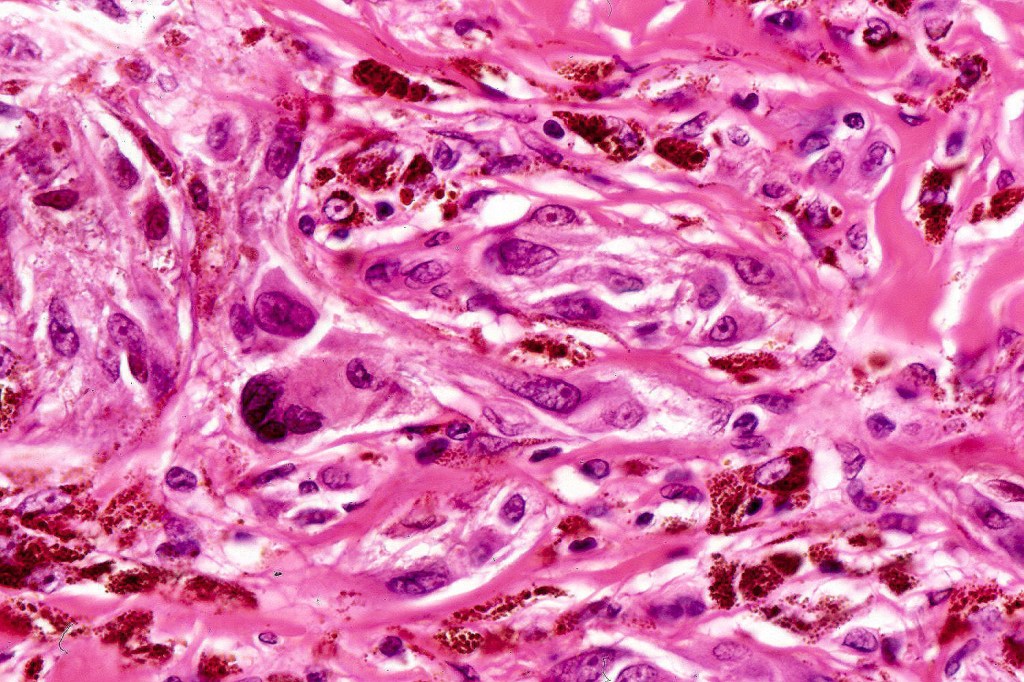

•Admixture of spindle cells, pigmented bipolar or dendritic cells & melanophages

•Cytoplasm is pale and nuclei are small with inconspicuous nucleoli

•Some tumors are composed spindle cells in a fascicular or neuronevoid pattern

•Perineural involvement may be seen